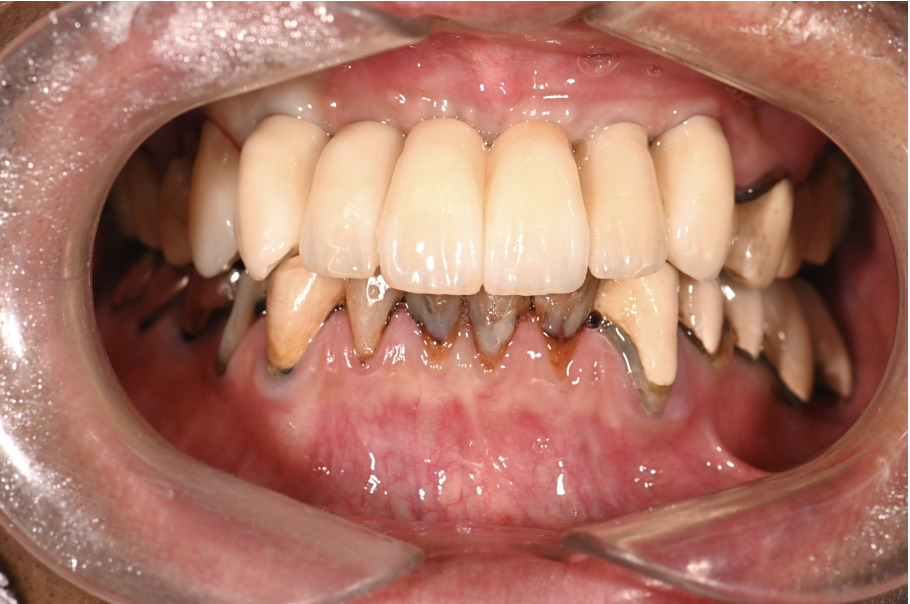

| 主訴 | 全体的にきれいにしたい |

|---|---|

| 治療内容 | 午前中に上下顎共に重度の歯周病、虫歯のため全ての歯を抜歯させていただき下顎はインプラントの土台を3本埋入し歯型を取り午後に上部構造(下顎全ての歯)を装着、上顎は一度総入れ歯を装着させていただきました。 治療が1日で完了しその日のうちに噛めるようになります。 |

| 治療期間 | 2回(1回目に資料取りをさせていただき2回目に下記の全ての治療をさせていただきました。) |

| 治療費 | 250万円 |

| 治療 リスク | 抜歯した部位などに関しては当日痛みが出ますので痛み止めなどを処方させていただきます |